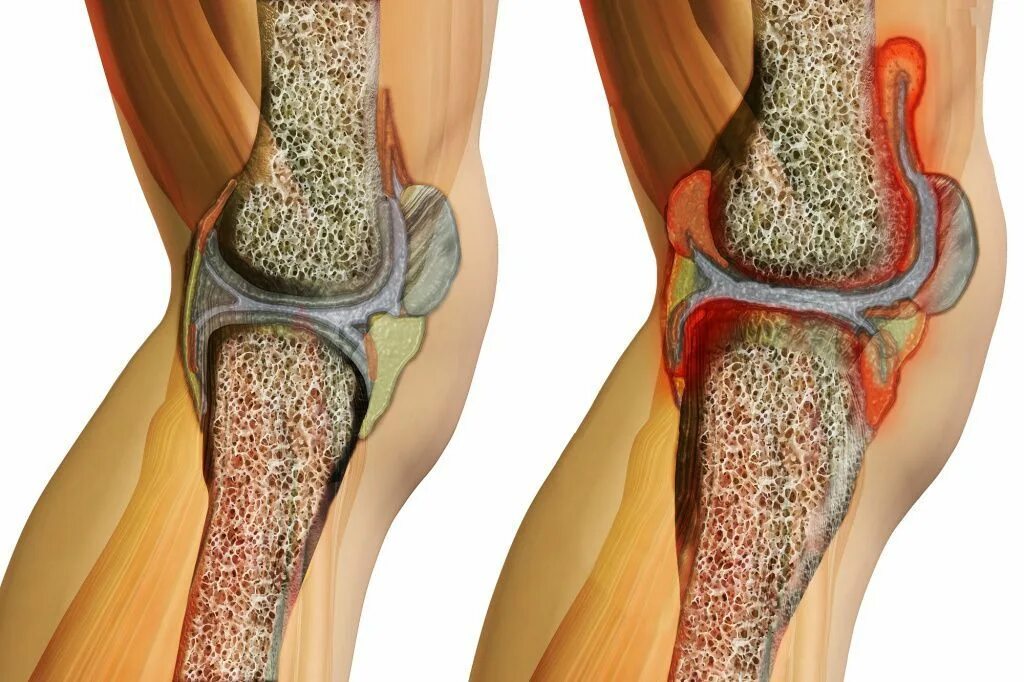

Артроз 2 степени симптомы